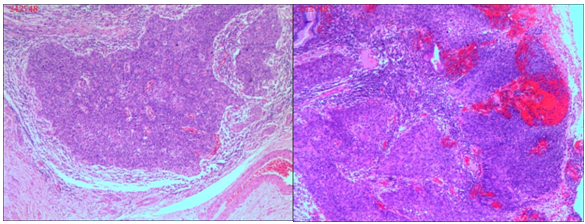

Figure 5 Pathology Slides: Examination of pathology specimen confirmed Cervical squamous cell carcinoma (non-keratinized), Stage IB1.

Pathology specimen was significant for a normal uterus and bilateral adnexa with a cauliflower-like cervical mass (3 x 2 x 0.7cm) (Figure 4). Histologic evaluation confirmed the diagnosis of cervical squamous cell carcinoma (non-keratinized), Stage IB1 (Figures 5A & 5B). The patient remained in the hospital for 10 days; three days to improve related auxiliary examinations and two days to improve bowel preparation. On the fifth day she received surgery in was discharged home in the tenth day, without complications.